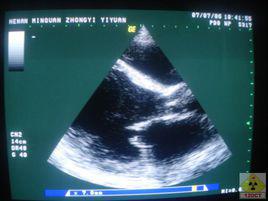

液性暗區( fluid sonolucent area)是指人體在做B型超聲檢查時,超聲在液體聚集的地方不容易穿過,在顯示器上可以看到的暗區。積液、積膿、羊水、血液等人體內的液體均可在B超下呈現為液性暗區。

如盆腔積液,胸腔積液,腹腔積液,心包積液等,在量較多是往往進行穿刺抽液。目的常常有兩個:1.協助診斷:對抽液進行生化病理方面的化驗以協助診斷積液的病因。2。治療:大量積液往往壓迫體內器官,引起生理情況的改變,造成疾病,抽出液體可不同程度緩解。